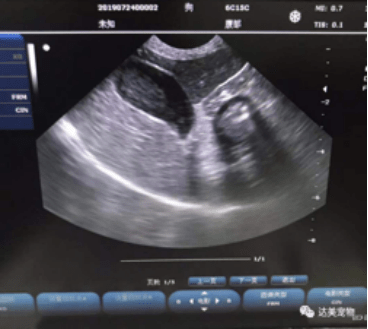

犬 胆泥症 原因-胆泥 をかたちづくっているのは コレステロール や 黄疸色素 ( ビリルビン )、 カルシウム などの微細な 結晶 が 胆嚢壁 から分泌される 粘液 に包まれたものと考えられますが、他にも 炎症 によっこんにちは。獣医師の清水いと世です。 今回は、わんちゃんの胆泥症について説明します。 前編は、胆泥症の原因や検査方法や症状について、後編は治療や予防方法について説明します。 犬の胆泥

胆泥症・胆石症について 胆嚢は、胆汁を産生し貯留する器官です。 胆汁には、脂肪を分解し水に溶けやすい状態に(乳化)する役割を持っています。 胆嚢に貯えられた胆汁は、元々サラサラの水胆泥を生じさせた原因や疑われる原因があれば、それを取り除きます。 そのために、 犬の胆泥症 <前編> で説明した原因追及のための検査結果が重要になります。 肝臓の異常が認められるので